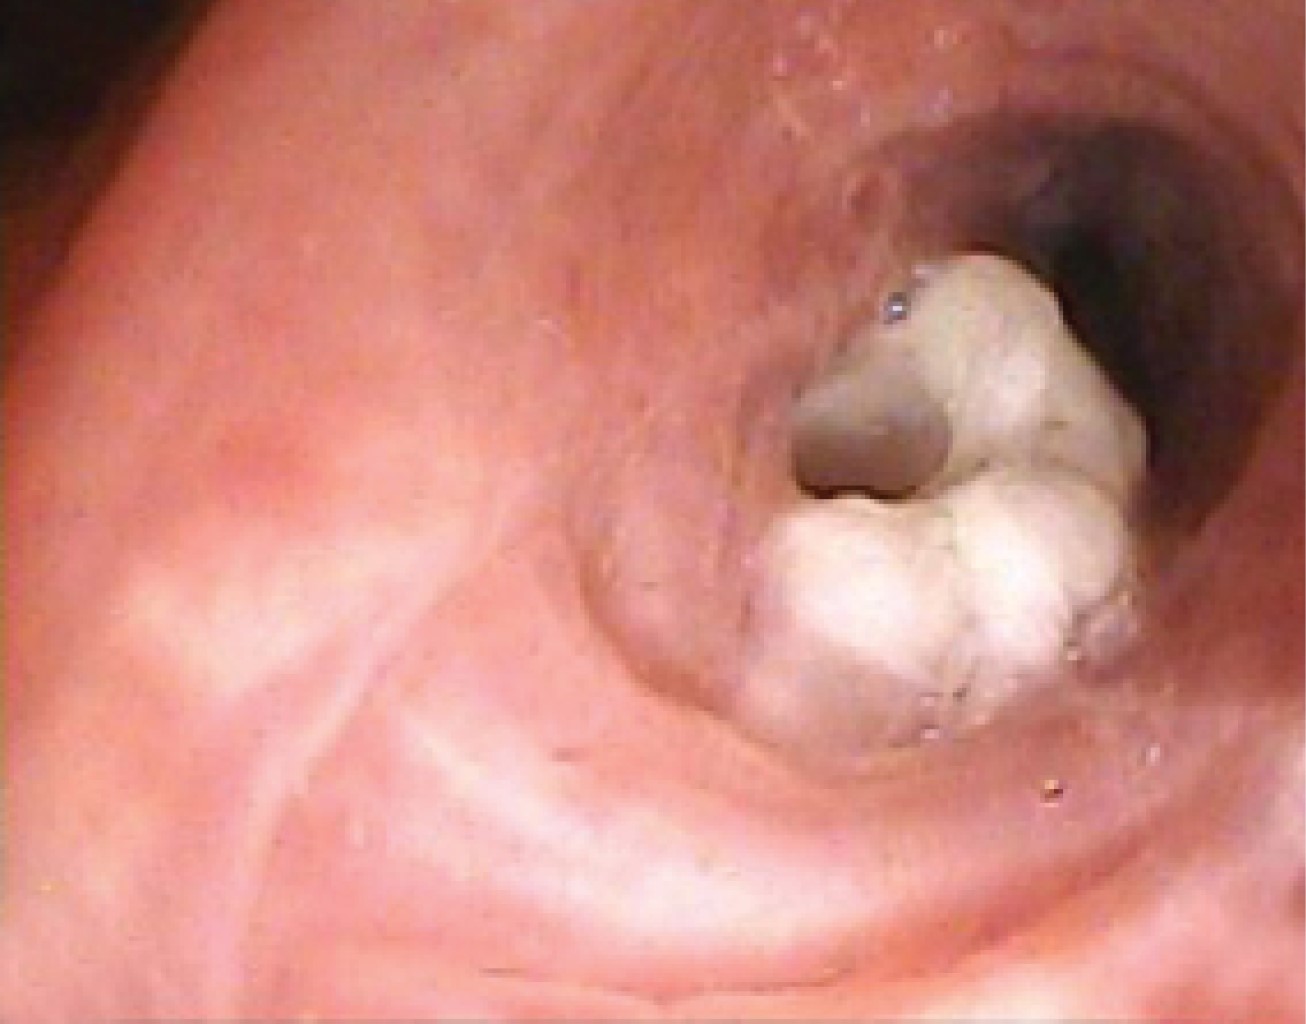

Hombre de 68 años de edad, el cual acude a nuestro hospital en julio 2023 por presentar tos no productiva con expectoración blanquecina, acompañada de disnea de medianos esfuerzos; niega fiebre, sufre pérdida de peso de 6 kg en las últimas semanas. Después de recibir tratamiento antiinfeccioso en el departamento de urgencias durante dos días, con poca mejoría, ingresó a neumología para protocolo diagnóstico y terapéutico; se tomó radiografía de tórax al momento de su ingreso (Figura 1); se programó estudio tomográfico de tórax (Figura 2), donde se encontró masa cavitada bien definida dentro del lóbulo superior izquierdo, con el signo de la media luna de aire. Por sospecha diagnóstica de tuberculosis pulmonar, se solicitó estudio de broncoscopia para lavado broncoalveolar y prueba de bacilos ácido-alcohol resistentes (BAAR), cultivo de micobacterias y de hongos, así como de bacterias. Durante el estudio con fibrobroncoscopia se observó una masa exofítica blanquecina en la pared anterior segmento S3 izquierdo, por lo que se decidió toma de biopsia y de muestras (Figura 3); posteriormente, mediante estudio histopatológico, se realizó el diagnóstico de mucormicosis y, por cultivo, mucormicosis Absidia. Se inició manejo con anfotericina B; durante los primeros tres días de iniciado el tratamiento, el paciente aumenta requerimiento de oxígeno, se solicita nueva radiografía de tórax; llega a mascarilla reservorio 15 litros con saturación de 90% con taquipnea, frecuencia respiratoria 30 por minuto, con disociación toracoabdominal, por lo que se decide manejo avanzado de la vía aérea. Fallece por choque séptico en sus primeras 12 horas de estancia en terapia intensiva respiratoria.

La mucormicosis pulmonar se desarrolla a causa de la inhalación de esporas de hongos en los bronquiolos y los alvéolos, lo que generalmente conduce a una rápida progresión de la neumonía o la enfermedad endobronquial. En casos poco comunes, esta infección puede llevar a lesiones endobronquiales y complicaciones asociadas con la obstrucción de las vías respiratorias. La hemoptisis es un síntoma común cuando se produce invasión vascular, lo que en ocasiones puede ser mortal. Los síntomas de la mucormicosis pulmonar suelen ser inespecíficos, incluso en las etapas avanzadas de la infección, y pueden incluir fiebre, disnea, tos y dolor torácico. En raras ocasiones, la enfermedad puede manifestarse como enfisema subcutáneo progresivo, síndrome de Pancoast, síndrome de Horner o mediastinitis crónica y perforación bronquial.6,9

Desde un punto de vista histopatológico, la invasión vascular con necrosis tisular e infiltración neutrofílica del tejido es común en todos los tipos de mucormicosis. El diagnóstico se logra al demostrar la presencia de hifas anchas (con un diámetro de 6 a 16 μm), no septadas (cenocíticas), en forma de cinta, con ramificación en ángulo recto en una muestra de tejido teñida con hematoxilina y eosina de rutina. Por lo general, no son necesarias tinciones especiales para hongos para establecer el diagnóstico. Las características menos comunes y menos específicas de la mucormicosis pulmonar incluyen invasión bronquial, neumonía, abscesos pulmonares y neumonitis granulomatosa.7